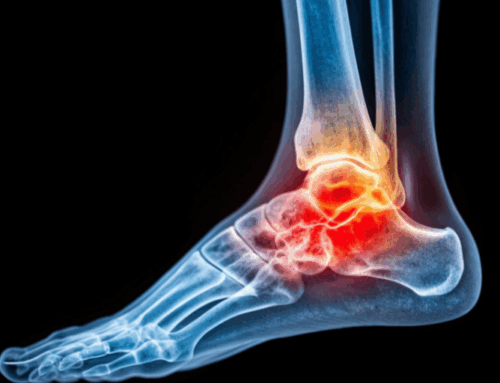

An ankle sprain involves stretch or tear of the ligaments that support the joint. Even milder sprains can feel frustrating, and more significant injuries may affect everyday activities. Early guidance from a qualified clinician helps you understand what’s going on and the general steps that support steady progress.

- Pain along the bones, not just the soft tissue: Discomfort on or near the bony parts of the ankle/foot can prompt imaging to rule out fractures.

Beyond a hands-on exam, your care team may recommend imaging to understand the extent of the injury. From there, you’ll get a plan matched to your goals and daily demands. People often appreciate knowing what activities to prioritize—and when—so the joint feels progressively more stable over time.

While many sprains improve with non-operative care, some injuries—like those with loose fragments, cartilage involvement, or persistent instability—may lead to a discussion of surgical options. If you’re researching advanced care, you can browse our high-level page on ankle arthroscopy for a general overview.